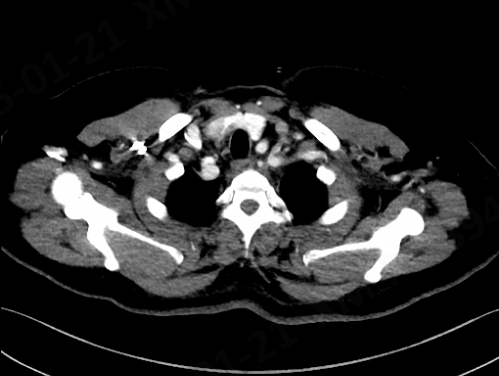

CT辅助检查:

1. Stanford B型胸主动脉夹层;

2. 弓降部壁内血肿形成。

CTA三维重建

CT平扫